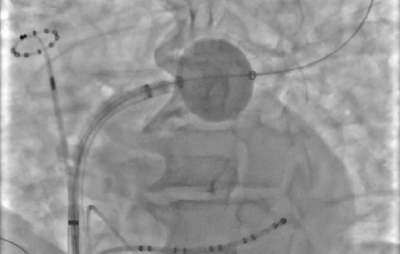

在X射線下,PFBalloon 的形態(tài)可以根據(jù)肺靜脈的不同解剖結(jié)構(gòu)進(jìn)行調(diào)整,展現(xiàn)出“橄欖形”、“球形”或“南瓜形”的形態(tài),這種形態(tài)的多樣性使得醫(yī)生能夠靈活地進(jìn)行消融操作。

PF Balloon在肺靜脈不同部位X線下的形態(tài)